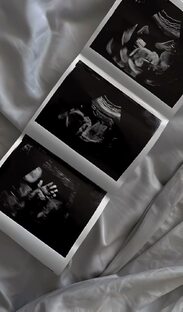

ЭКО: что это и как оно помогает стать мамой или папой

Привет! Сегодня поговорим о таком важном и иногда сложном вопросе — экстракорпоральное оплодотворение, или просто ЭКО. Если вы сталкиваетесь с проблемами с зачатием или просто хотите понять, что это за процедура, эта статья для вас. ЭКО — это метод помощи в зачатии, когда оплодотворение происходит вне тела женщины. Представьте: врачи берут яйцеклетки у женщины и сперматозоиды у мужчины, соединяют их в лабораторных условиях, а потом возвращают полученные эмбрионы в матку. Всё это делается, чтобы помочь паре стать родителями, если у них есть сложности с естественным зачатием...